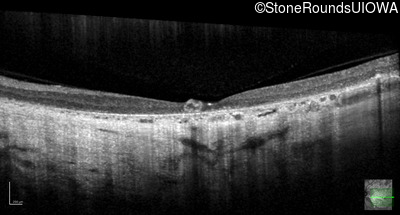

Optical Coherence Tomography - Right - 20/63

Exemplar / OCT Stack